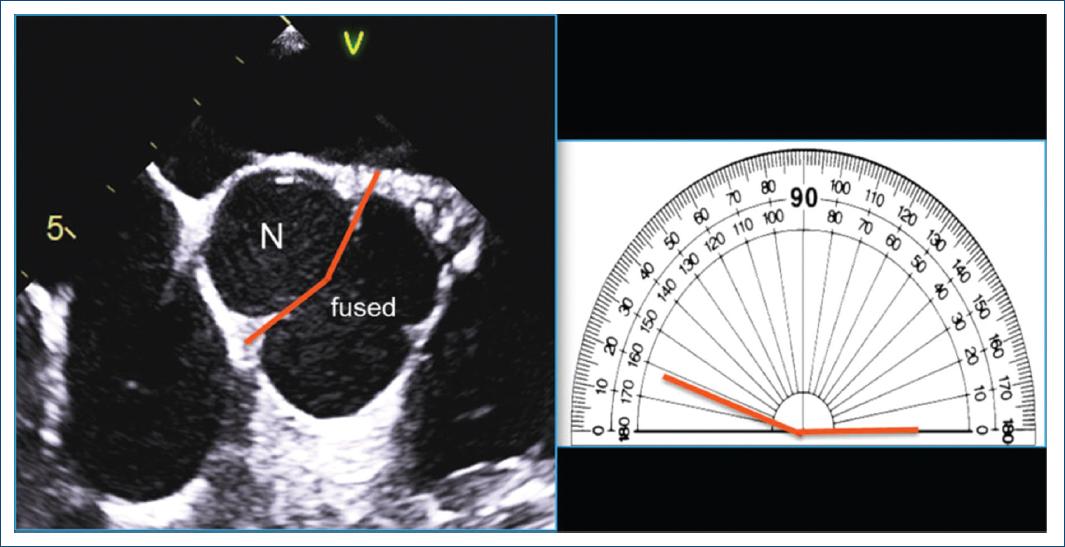

La simetría de la VAB para el tipo fusionado se define por el ángulo entre las comisuras de la cúspide no fusionada y recientemente se ha convertido en un aspecto crítico en la planificación de la reparación de la VAB para la insuficiencia aórtica pura6,20,44. Desde la perspectiva del tratamiento de la insuficiencia, el «concepto» de VAB ofrece una superficie de coaptación de una sola línea (una válvula aórtica tricúspide tiene tres líneas de coaptación [Fig. 5, izquierda]); siempre que esa única línea de coaptación sea recta o casi recta (Figs. 8 y 9-simétrica), la reparación de la VAB insuficiente es simple y reproducible. A medida que el ángulo entre las comisuras de la cúspide no fusionada disminuye < 160°44, la VAB se vuelve menos simétrica, pareciéndose más a una válvula tricúspide (especialmente < 140°) (Fig. 9, muy asimétrico), que se vuelve técnicamente más difícil para el cirujano «bicuspidizar» durante la reparación, pero sigue siendo reparable en manos experimentadas. Las válvulas asimétricas pueden exhibir retracción del borde libre de la cúspide fusionada a nivel del rafé, lo que se aprecia mejor mediante la visualización quirúrgica directa (Figs. 2 y 9) o inspección patológica, pero no se aprecia confiablemente por imágenes. Esta retracción puede contribuir a la insuficiencia de la válvula. La medición del ángulo comisural de la cúspide no fusionada con TEE antes de la derivación cardiopulmonar ayuda al cirujano a planificar la reparación (Fig. 10). Por lo tanto, la simetría de una VAB de tipo fusionado se define por el ángulo entre las comisuras de la cúspide no fusionada y es un parámetro crítico para la reparación quirúrgica de la VAB regurgitante.

Figure 10 Medición ecocardiográfica transesofágica del ángulo comisural de la cúspide no fusionada antes de la reparación de la válvula. Aplicable a vistas tomográficas similares obtenidas mediante tomografía computarizada cardiaca y resonancia magnética cardiaca, después de una cuidadosa visualización del movimiento sistólico y diastólico de esta válvula aórtica bicúspide insuficiente de tipo fusionada derecha-izquierda (fused), se identifican las comisuras no fusionadas y se dibuja una línea desde la posición de las comisuras hasta el centro de la válvula en la diástole (izquierda). El ángulo de la cúspide no fusionada (N) se mide cuidadosamente a aproximadamente 162° en el transportador a la derecha, lo que sugiere una buena posibilidad de reparación (modificada de Michelena et al., 201811 con permiso de Elsevier).